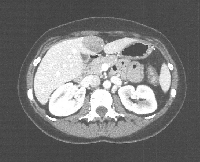

Πρόκειται για γυναίκα ασθενή 32 ετών η οποία, στα πλαίσια γυναικολογικής λαπαροσκόπησης, διαπιστώθηκε ότι έφερε στο 4ο ηπατικό τμήμα ευμεγέθη βλάβη. Η τριφασική MDCT ήπατος που ακολούθησε ανέδειξε μονήρες αδένωμα μεγέθους 5 cm σε επαφή με τον ηπατοδωδεκαδακτυλικό σύνδεσμο (εικόνα 1). Η ασθενής υποβλήθηκε σε λαπαροσκοπική (HALS) εκτομή του ηπατικού τμήματος 4b και σε χολοκυστεκτομή (εικόνα 2). Η διατομή του ηπατικού παρεγχύματος έγινε με τη χρήση αυτορυθμιζόμενης διπολικής διαθερμίας (εικόνα 3) και αυτόματου λαπαροσκοπικού αγγειακού κοπτοπάπτη (εικόνα 4). Διενεργήθηκε συμπλησίαση της επιφάνειας διατομής με τη χρήση ραμμάτων (εικόνα 5). Το παρασκεύασμα δεικνύεται στην εικόνα 6. Η ασθενής έλαβε εξιτήριο την 3η μετεγχειρητική ημέρα.